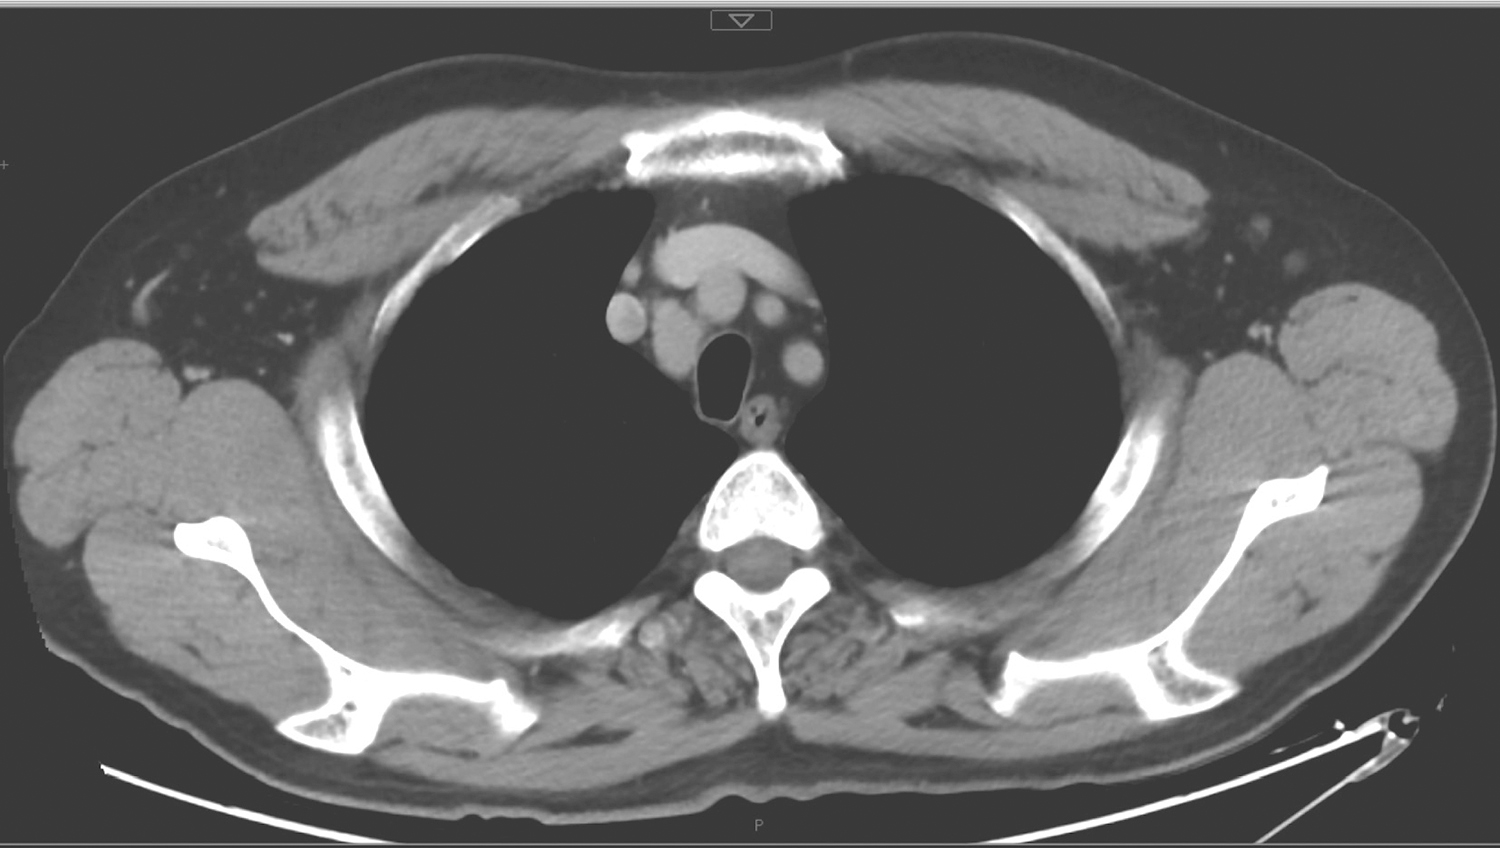

2.2017年5月15日颈胸部CT

甲状腺右叶低密度结节,约3.2cm×2.2cm,边界欠清楚,右侧气管壁受压,管腔受压略左移(图3);右侧气管食管沟、双侧锁骨上区及上纵隔多发淋巴结影,大者短径约1.5cm(图4);双下肺条索影,余双肺及纵隔未见明确结节或实变;双侧肺门未见明确肿大淋巴结;双侧胸腔、心包未见积液。

图4 胸部CT示上纵隔多发淋巴结影

影像学诊断:

(2)右气管食管沟、双侧锁骨上区及上纵隔多发淋巴结影,需警惕转移。